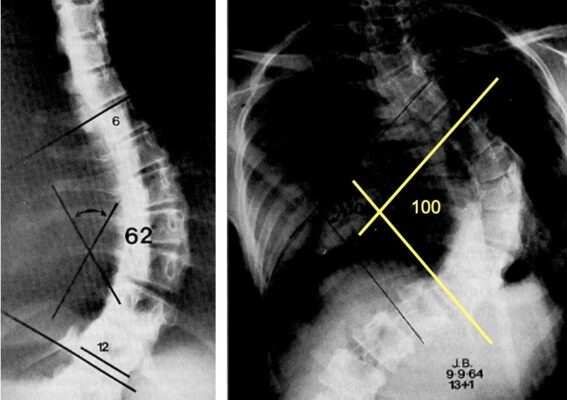

- Chụp X quang thẳng, nghiêng từ chẩm đến xương cụt nhằm xác định vị trí và mức độ vẹo cột sống (đo góc Cobb).

- Dựa vào X quang: Đánh giá mức độ vẹo cột sống theo phương pháp Cobb :

- Vẹo nhẹ: cong dưới 20 0 (cong dưới 100 vẫn được xem là ở phạm vi bình thường chưa cần phải điều trị).

- Vẹo trung bình: cong từ 200 đến 40-500. Vẹo trung bình thường kèm theo những thay đổi ban đầu về cấu trúc của đốt sống và xương sườn.

- Vẹo nặng: >40-500. Hậu quả có thể gây đau và thoái hóa cột sống về sau, giảm chức năng tim phổi và tuổi thọ.

- Đường cong < 30 º vào tuổi trưởng thành xương ít khi tiến triển

- Đường cong >50 º vào tuổi trưởng thành xương sẽ tăng 1º mỗi năm

- Hậu quả lên chức năng tim phổi xuất hiện khi đường cong càng lớn, khi đường cong >100 º